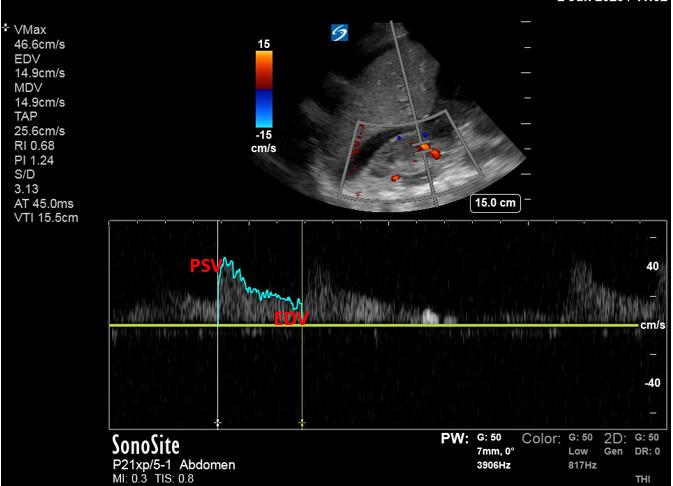

急性肾损伤(AKI)对于入住重症监护病房(ICU)的患者而言是一个重大问题,这是由于其发病率高且伴有死亡率,需要肾脏替代治疗(RRT)的AKI发生率超过5%,而AKI的死亡率超过60%[1,2]。超声可用于识别有AKI风险的患者并辅助进行AKI管理。ICU中AKI的危险因素不仅包括低灌注,还包括静脉淤血和容量超负荷。容量超负荷和血管淤血与多器官功能障碍及更差的肾脏预后相关。每日及总体液体平衡、每日体重以及水肿的体格检查可能不准确,且会掩盖真正的全身静脉压[3,4,5]。床旁超声可让医护人员评估血管血流模式,并对容量状态进行更可靠的评估,以指导并个体化治疗。超声检查的心脏、肺部和血管模式可识别前负荷反应性,应评估前负荷反应性以安全地管理正在进行的液体复苏,并评估液体不耐受的迹象。在此,我们概述了床旁超声的应用,特别强调以肾脏为中心的策略,即在识别肾损伤类型、评估肾血管血流、静态测量容量状态以及对危重症患者进行容量优化的动态评估方面的应用。